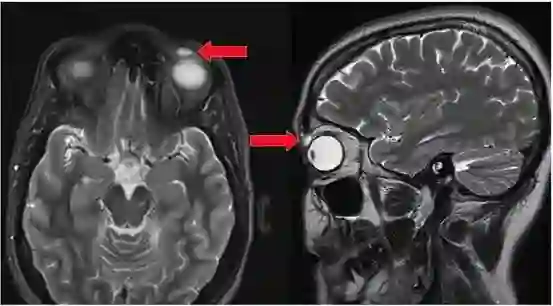

西雅图的一名妇女患上了罕见且致命的“食脑”阿米巴原虫感染,或由于不正确使用洗鼻器所致。据悉,这位69岁的妇女一直在用洗鼻器冲洗鼻子,但用的溶液却不是推荐使用的无菌水或盐水溶液。不久,她鼻子上长了一个小疹子,且不会消失。一年后,该女子突发癫痫。

起初,医生认为她患有脑瘤,但测试显示她感染了一种叫做阿米巴(Balamuthia mandrillaris)的变形虫。这类感染非常罕见,自1993年以来,美国仅报告了约70例。医生怀疑这名妇女是经未消毒的自来水中感染的。

该病例发表在12月号的《International Journal of Infectious Diseases》杂志上。